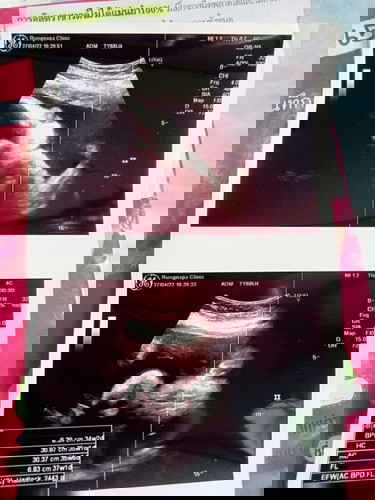

35วีค ลูกหนัก 2448 หนักน้อยไปไหมคะ

บ้านนี้ 35 4 2577 คุณหมอบอกตามเกณฑ์นะคะแม่ ไม่ต้องกังวลนะคะ บำรุงได้อีกเยอะจ้า